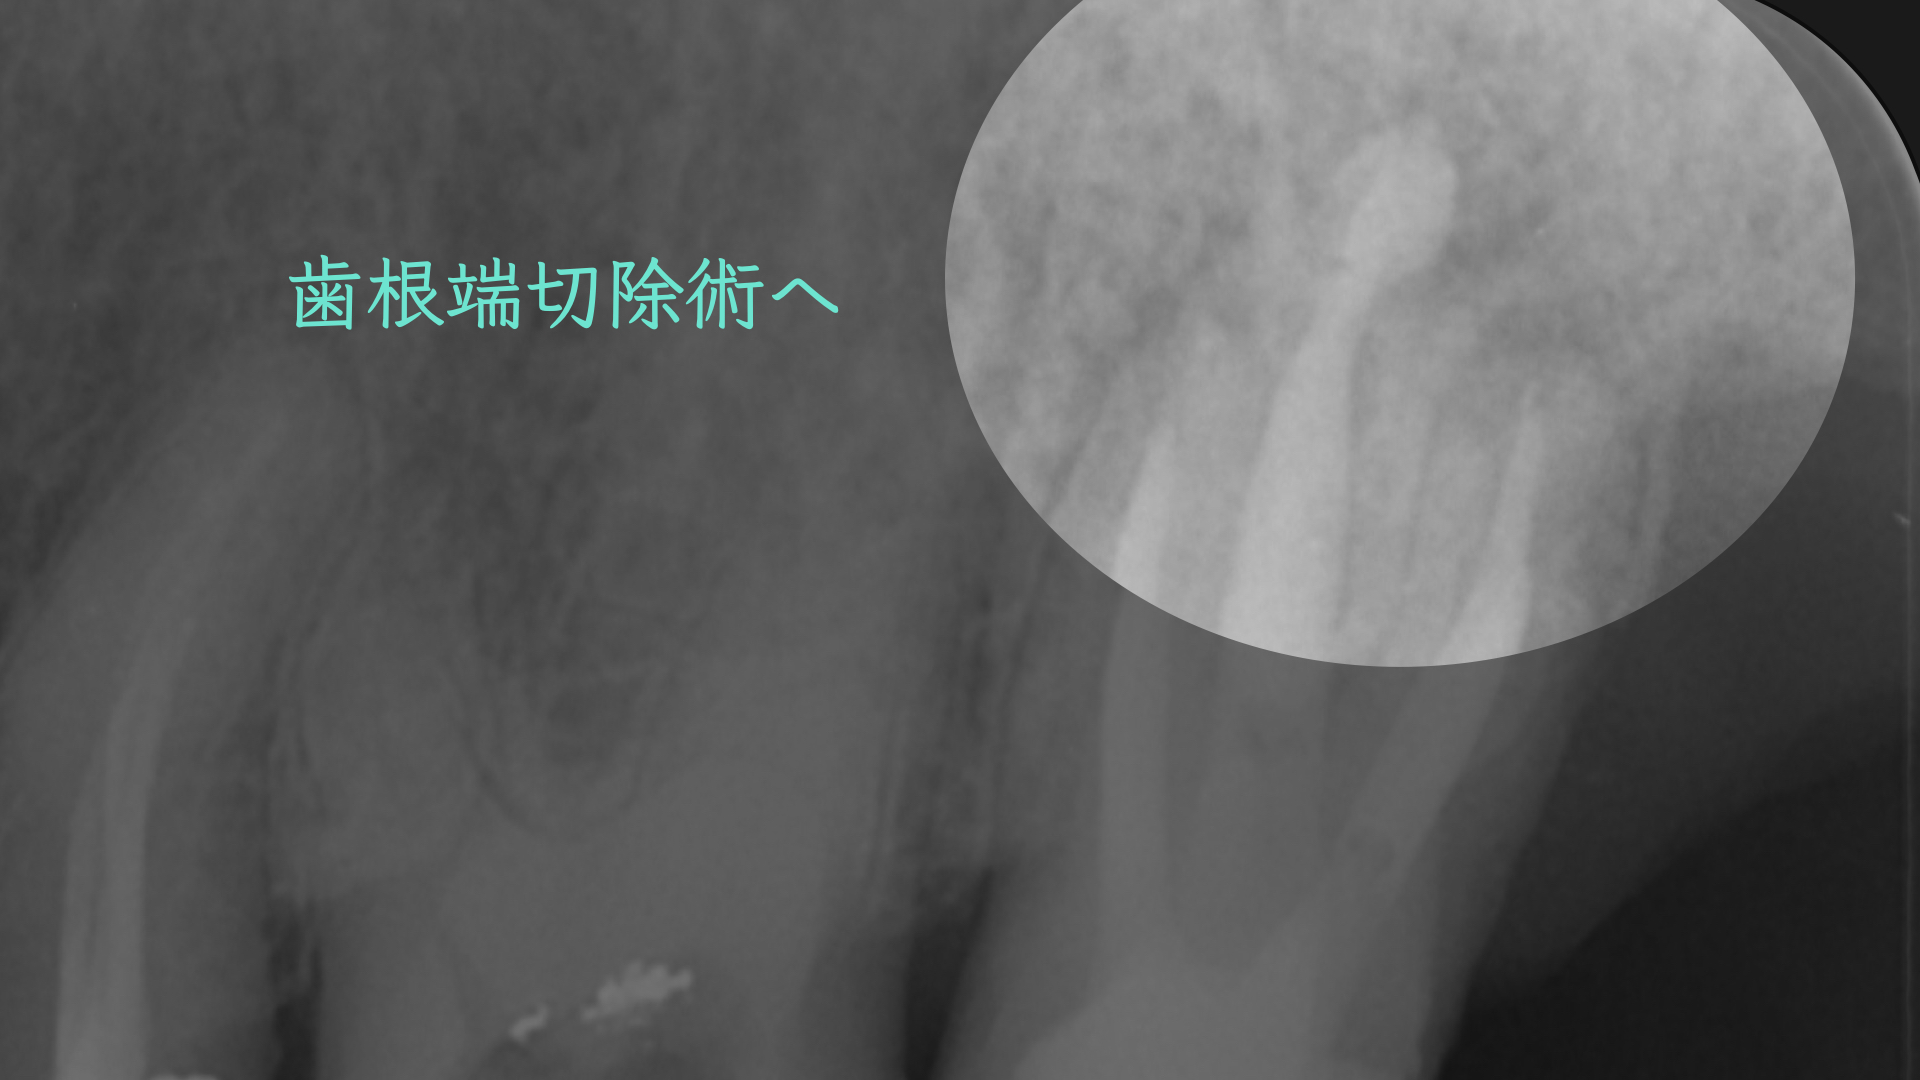

患者さんの都合もあり1年後に歯根端切除(外科的歯内療法)をおこなうことになりました。

教科書によると、この部位は適応症でなく、一般的には意図的再植の適応症にはなりますが、このような歯根が離開している歯を一度抜歯するのは破折のリスクがあります。

適応症ではないのは大口蓋動脈の存在です。

論文より今回のケースは安全であると判断し、歯根端切除で対応しました。

切断した歯根です。表面が粗造になっており、感染が根尖孔外にあったことを認めます。

注意しておこないました。

術後、歯根は骨に囲まれるように治癒にしました。

このように非外科的な治療のみでは治癒に導けない場合は、外科的歯内療法で保存できる可能性があります。